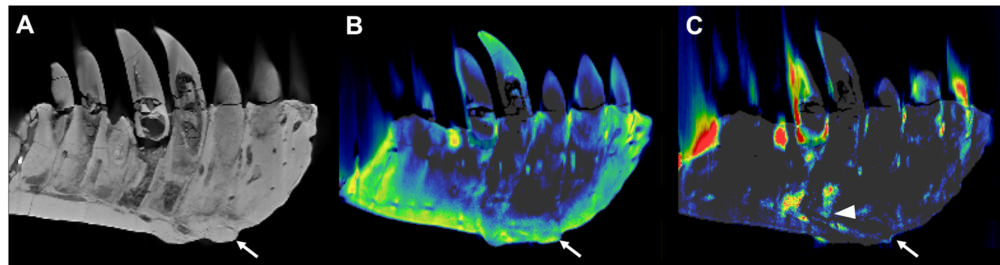

On visual inspection and CT imaging, the left dentary showed thickening and a mass on its surface that extended to the root of one of the teeth. DECT detected a significant accumulation of the element fluorine in the mass, a finding associated with areas of decreased bone density. The mass and fluorine accumulation supported the diagnosis of tumefactive osteomyelitis, an infection of the bone.

Figure 2. CT reconstructions of the tooth-bearing part of the left dentary. (A) Reconstruction of the conventional CT images in lateral view showing well-preserved anatomical structures such as the replacement teeth. The arrow indicates the focal exophytic mass—the abnormal growth that sticks out from the surface of the tissue—on the ventral surface at the level of the 3rd to 5th tooth roots. (B) The DECT-based calcium material map shows a homogeneous mineral distribution, while (C) the fluorine material map shows significant mineral accumulation in the center of the exophytic mass and adjacent tooth roots (arrowhead).